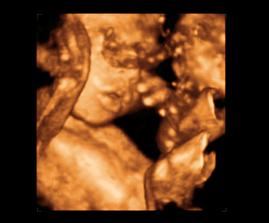

26 tt../1.4.2009/ naša paulínka je stráášne zlatá, boli sme si pozrieť na 4D utz. ..tvárila sa veľmi dôležito, až nafúkano...hehe..vôbec sa nechcela usmievať... nakoniec sa nám aj zasmiala...v brušku veľmi vyvádza, maminke dosť vytláča všetky časti telíčka, čo je niekedy aj dosť bolestivé...ale vydržíme, drobečkovi je tam určite tiež pritesno..a ešte aj stále viac a viac bude... strááášne sa na ňu tešíme🙂))